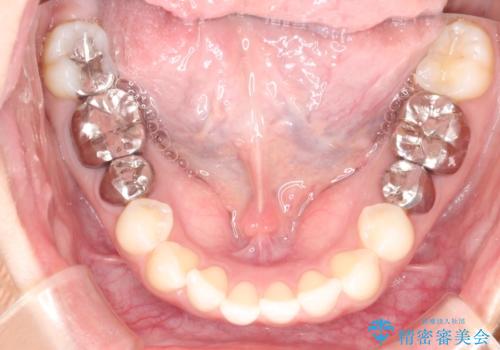

【メタルフリー】銀歯を白くしたい。オールセラミッククラウン。

- 銀歯を白くしたいと希望され来院されました。

すぐにでも白くしたいとのことで、2回目の来院で銀歯を白い仮歯に変更し喜んでいただきました。

ただ単純に白くするでけではなく拡大鏡を使用し、丁寧な処置を行なっております。